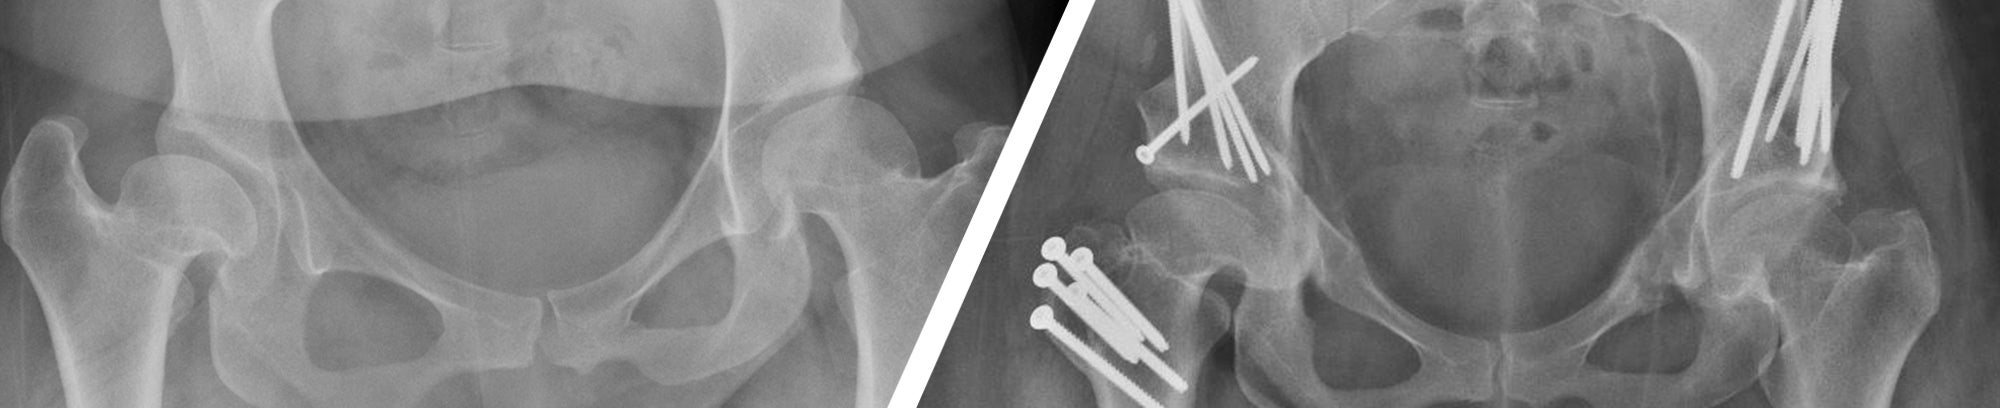

El Centro de Ortopedia de Valley Children's cuenta con el primer Programa para el Cuidado de la Cadera para bebés, niños, adolescentes y adultos jóvenes de hasta 35 años en el Valle Central. Nuestro programa se especializa en el diagnóstico y el tratamiento de todos los trastornos de la cadera.

Ofrecemos una gran variedad de opciones de tratamiento para trastornos de cadera frecuentes y complejos. Tratamos a bebés y niños con trastornos congénitos, del desarrollo y postraumáticos de la cadera mediante el acceso a intervenciones de vanguardia sin tener que viajar fuera del Valle.

Los especialistas en ortopedia de Valley Children's tratan una gran variedad de anomalías de la cadera en adolescentes y adultos jóvenes de hasta 35 años. Las enfermedades frecuentes y complejas de la cadera suelen pasar desapercibidas en la primera infancia y es posible que no se diagnostiquen hasta que aparezca dolor crónico u otros síntomas durante la adolescencia y los primeros años de la edad adulta. Nuestros especialistas en preservación de la cadera reconocidos en todo el país ofrecen tratamientos que abarcan desde una intervención temprana para prevenir un mayor daño articular hasta una intervención quirúrgica compleja para reducir el dolor y mejorar el funcionamiento.